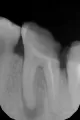

Стояла 8 лет пломба, она выпала, под ней почти ничего, осталось буквально две стенки и те почерневшие. Стою перед выбором: пытаться ли его лечить или удалять?

Врач сказал, что лечение при такой картине с двумя воспаленными корневыми каналами предстоит долгое и мучительное, с необходимостью разрезать десну. Вероятность того, что будут осложнения и в итоге зуб придется удалять, велика.

На верхушках корней, возможно, имеются изменения и открытая бифуркация.